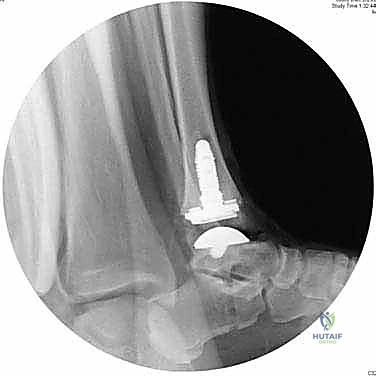

6. التحقق والإغلاق

يتم فحص المدى الحركي للكاحل الجديد وثباته تحت جهاز الأشعة السينية (Fluoroscopy) داخل غرفة العمليات للتأكد من المحاذاة المثالية بنسبة 100%. بعد ذلك، يتم إغلاق الشق الجراحي بغرز تجميلية، ووضع جبيرة ناعمة أو حذاء طبي واقٍ.